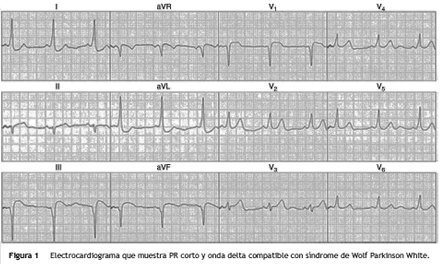

Las arritmias supraventriculares por reentrada por una vía accesoria evidente en el electrocardiograma de superficie (EKG), por la presencia de una onda delta y un PR corto, constituyen el síndrome de Wolff-Parkinson-White (WPW), cuyo manejo de elección una vez ha manifestado síntomas, es la realización de un estudio electrofisiológico con mapeo para ubicar la vía accesoria (haz de Kent) y su posterior ablación1, con tasas de éxito entre el 90 a 95%, dependiendo de la ubicación de la vía accesoria2.

Paciente de sexo femenino de 55 años de edad, sin antecedentes de importancia, quien había consultado en varias ocasiones por episodios de palpitaciones, documentándole taquicardia supraventricular paroxística, con evidencia en el EKG posterior a la taquicardia de PR corto y onda delta, por lo que se hace el diagnóstico de síndrome de WPW (fig. 1).